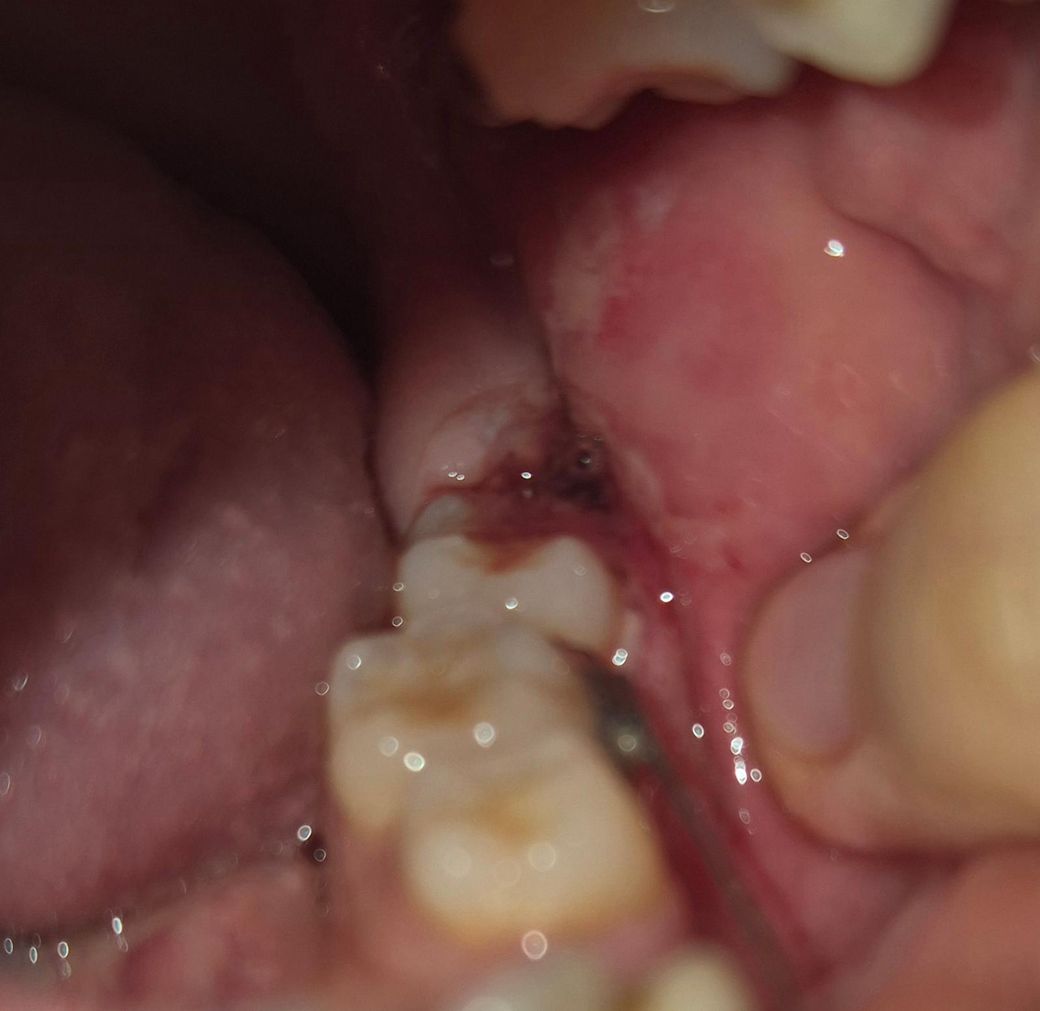

사랑니 발치 이틀차인데 계속 피나와요

어제 거즈 4번정도 갈면서 지혈했고 1번째 사진은 오전10시쯤밥, 약먹고 난뒤입니다. 거즈문 상태로 자고 4시쯤 일어나서 밥먹고 약먹었는데 피맛이 아니라 이상한 맛 나는데 감염된 걸까요? 2,3번째사진

• 1번 째 사진